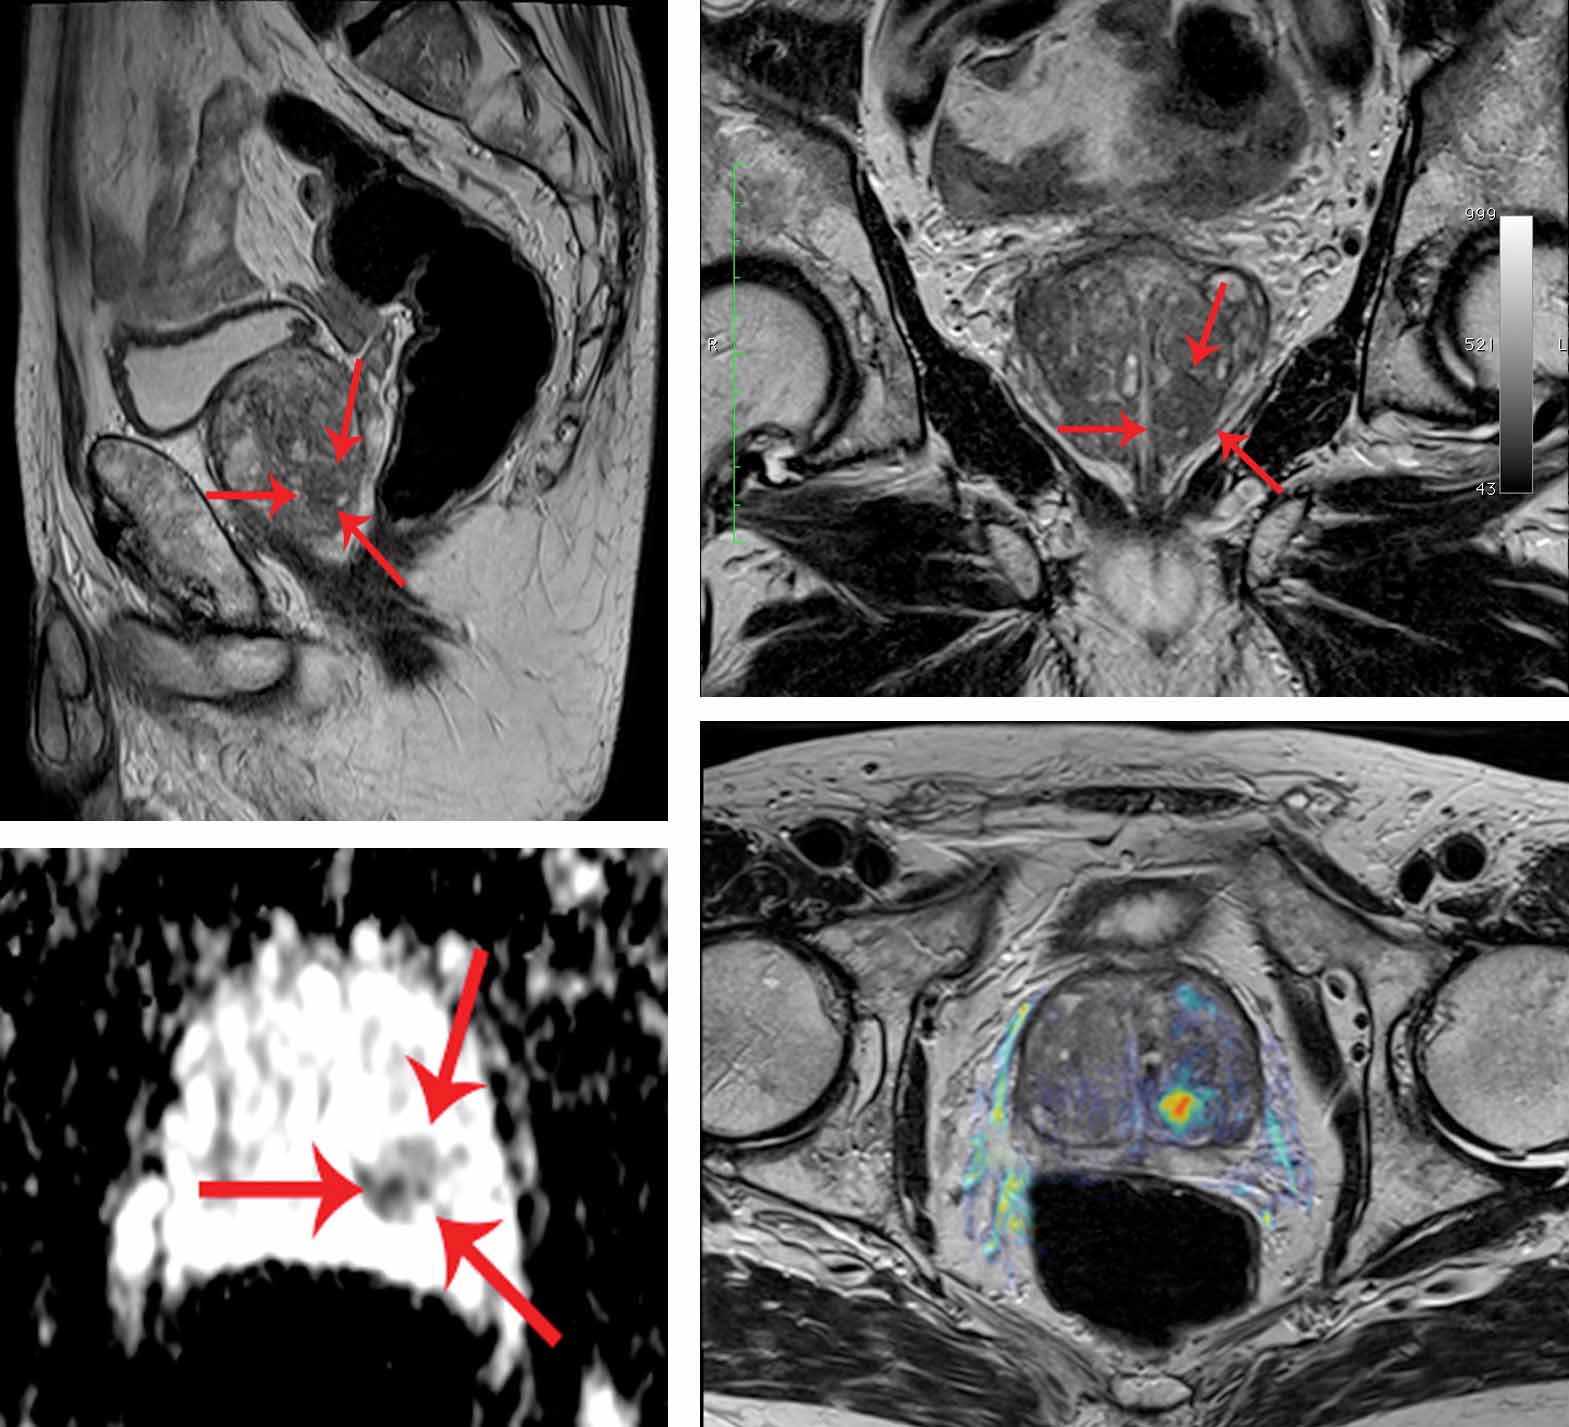

Лейомиосаркома матки мрт

Гранулезоклеточная опухоль яичника мрт

Примеры фото МРТ малого таза у женщин

Ниже представлены примеры фотографий МРТ малого таза у женщин, позволяющие увидеть, как выглядят снимки и какие изменения могут быть обнаружены специалистами.